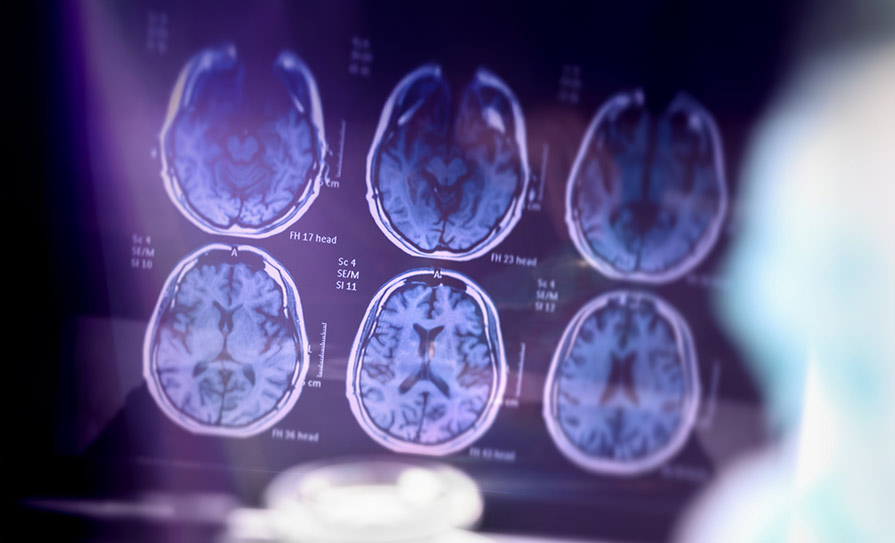

Patients will require MRI scans to monitor for ARIA prior to initiating treatment and before the fifth, seventh, and 14th dose. Additional MRI scans may be needed during treatment if patients develop symptoms of ARIA.